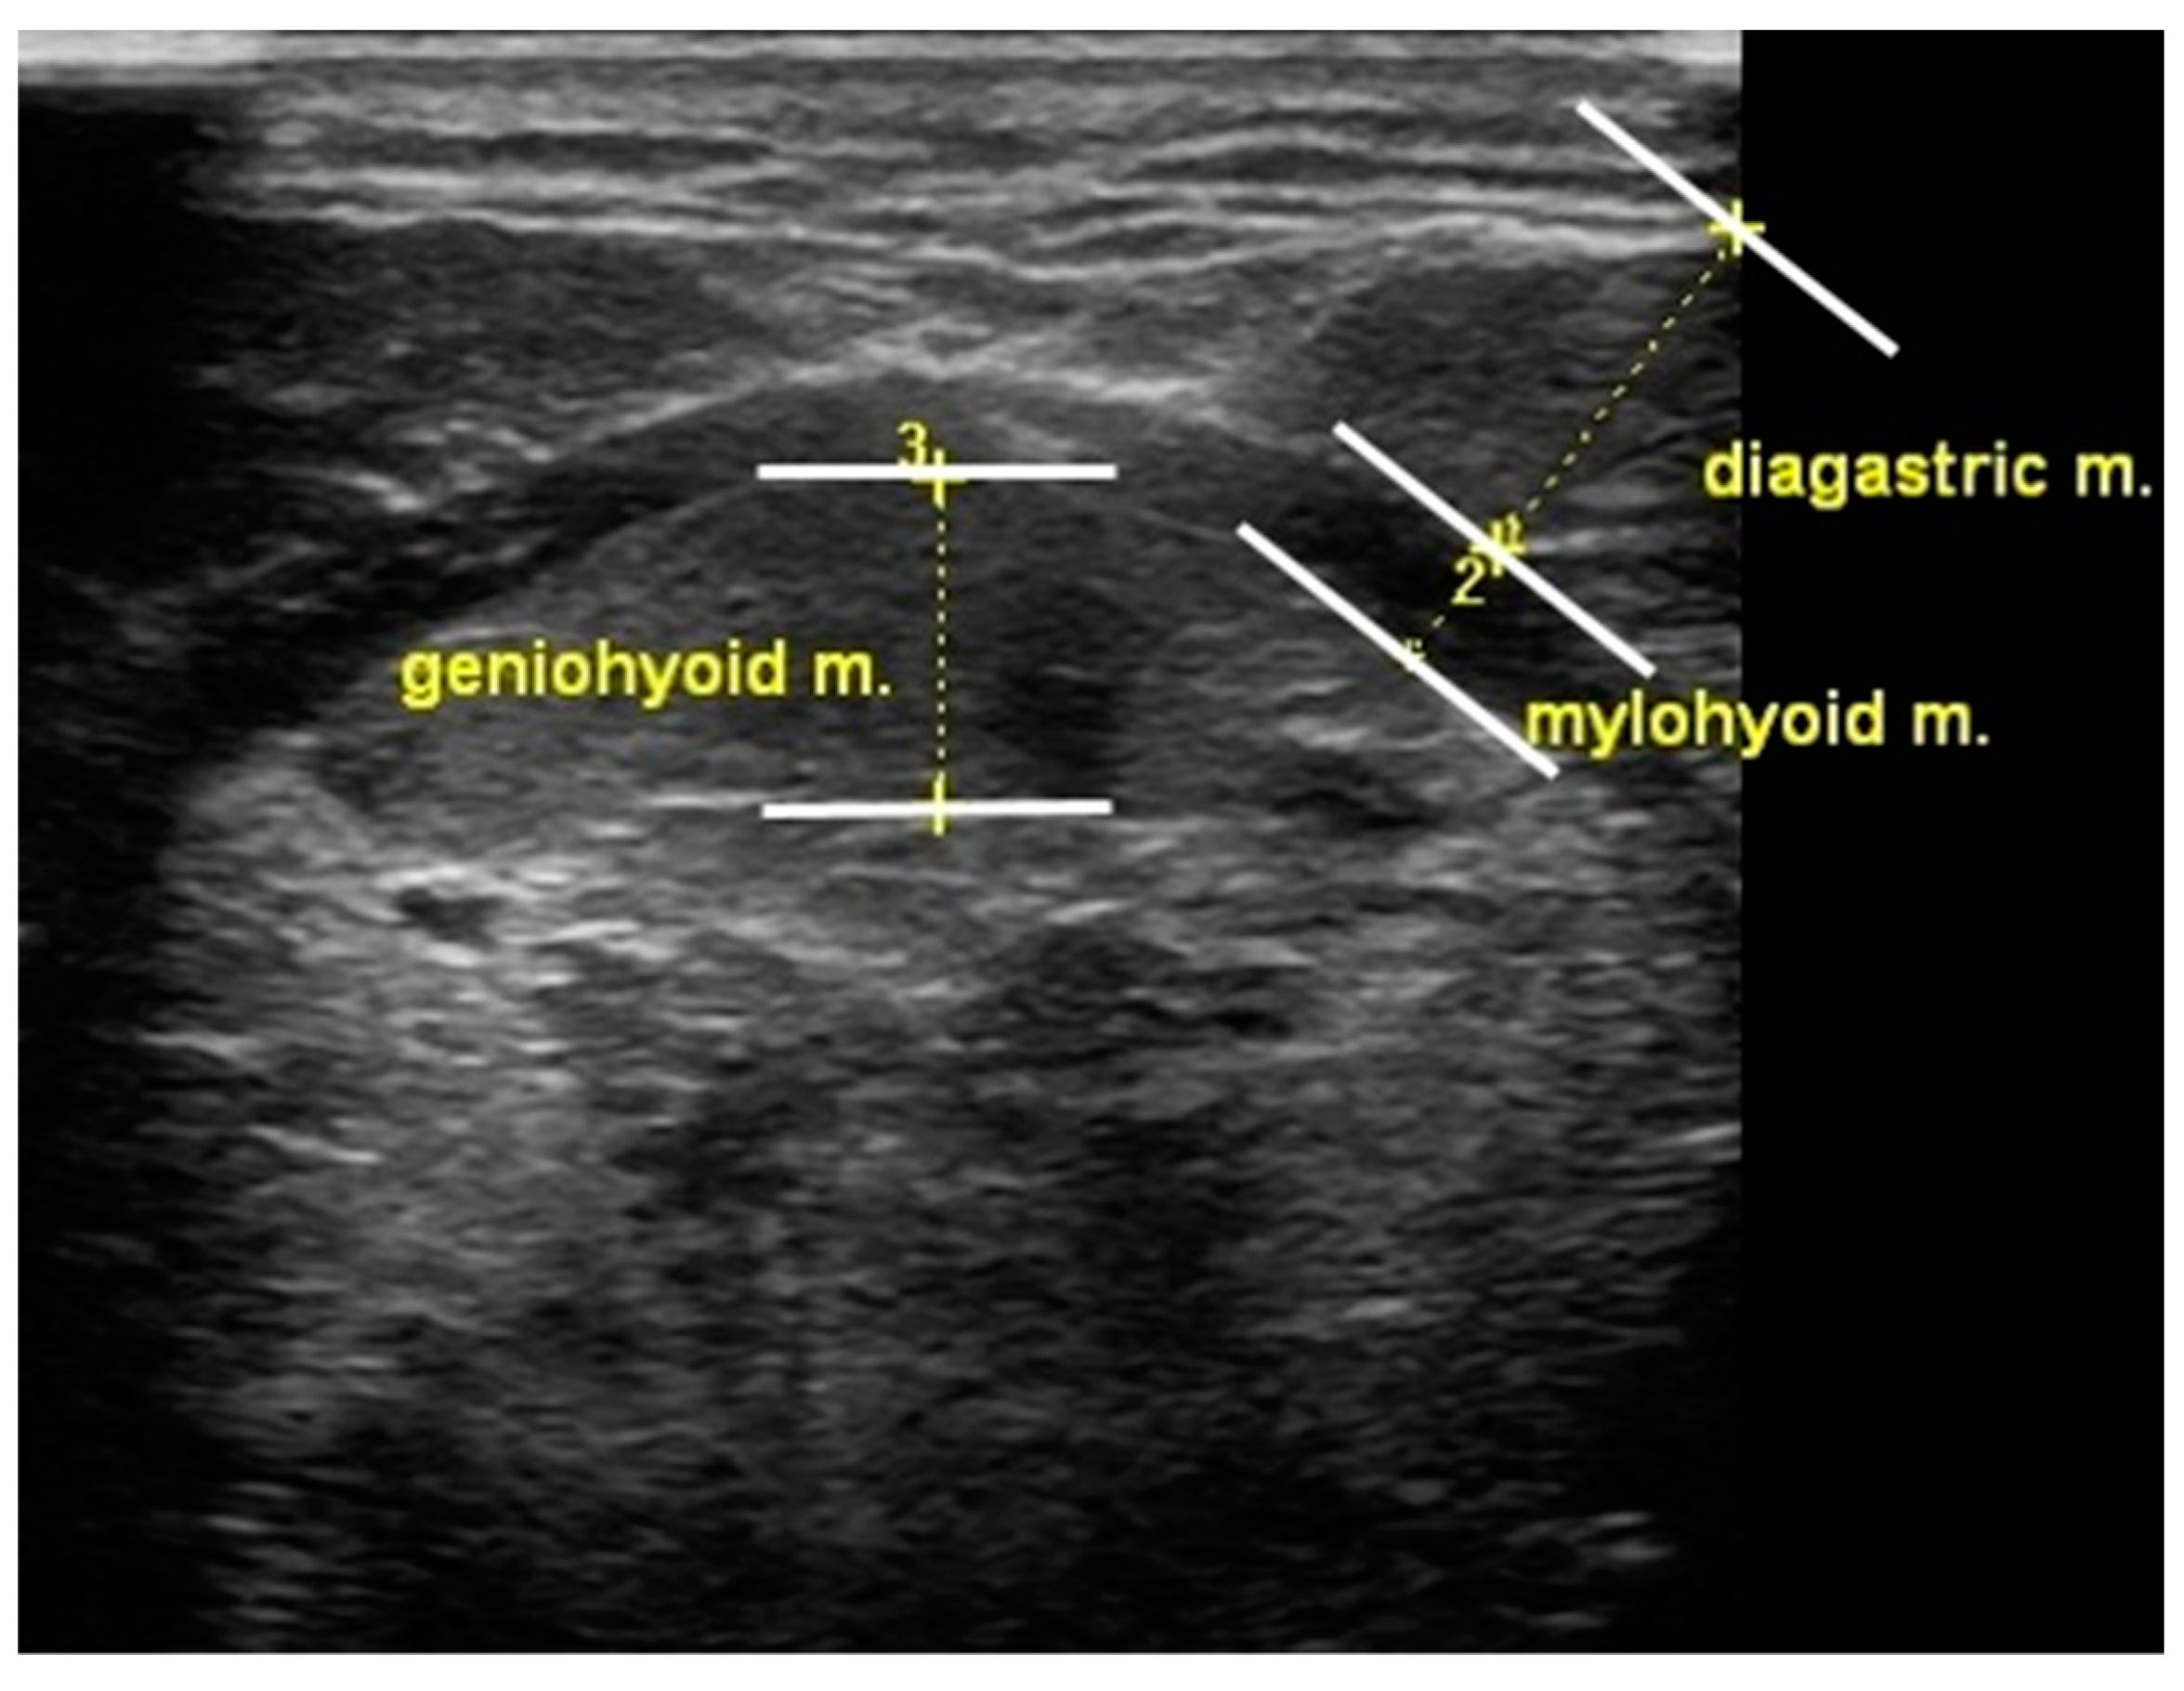

In this study, tongue and suprahyoid muscle thickness was measured using a portable ultrasonography device (SONON300L, Healcerion, Seoul, Korea) with a 10 MHz and linear- and convex-array transducer. Change in tongue thickness was determined by measuring the distance between the upper and lower surfaces of the tongue muscles in the center of the plane perpendicular to the Frankfort horizontal plane of the frontal session. The vertical distance was measured from the surface of the mylohyoid muscle to the dorsum of the tongue. The digastric muscle measurements were obtained from the upper to the lower boundary of the fascia covering the muscle at the broadest point perpendicular to the mylohyoid muscle. The mylohyoid muscle measurements were recorded below the measurement point of the digastric muscle, from the upper to the lower boundary of the fascia covering the muscle (Figure 2). A blinded investigator (rehabilitation physician) measured and analyzed the muscle thickness using ultrasound.

Figure 2. Measurement of oropharyngeal muscle thickness.